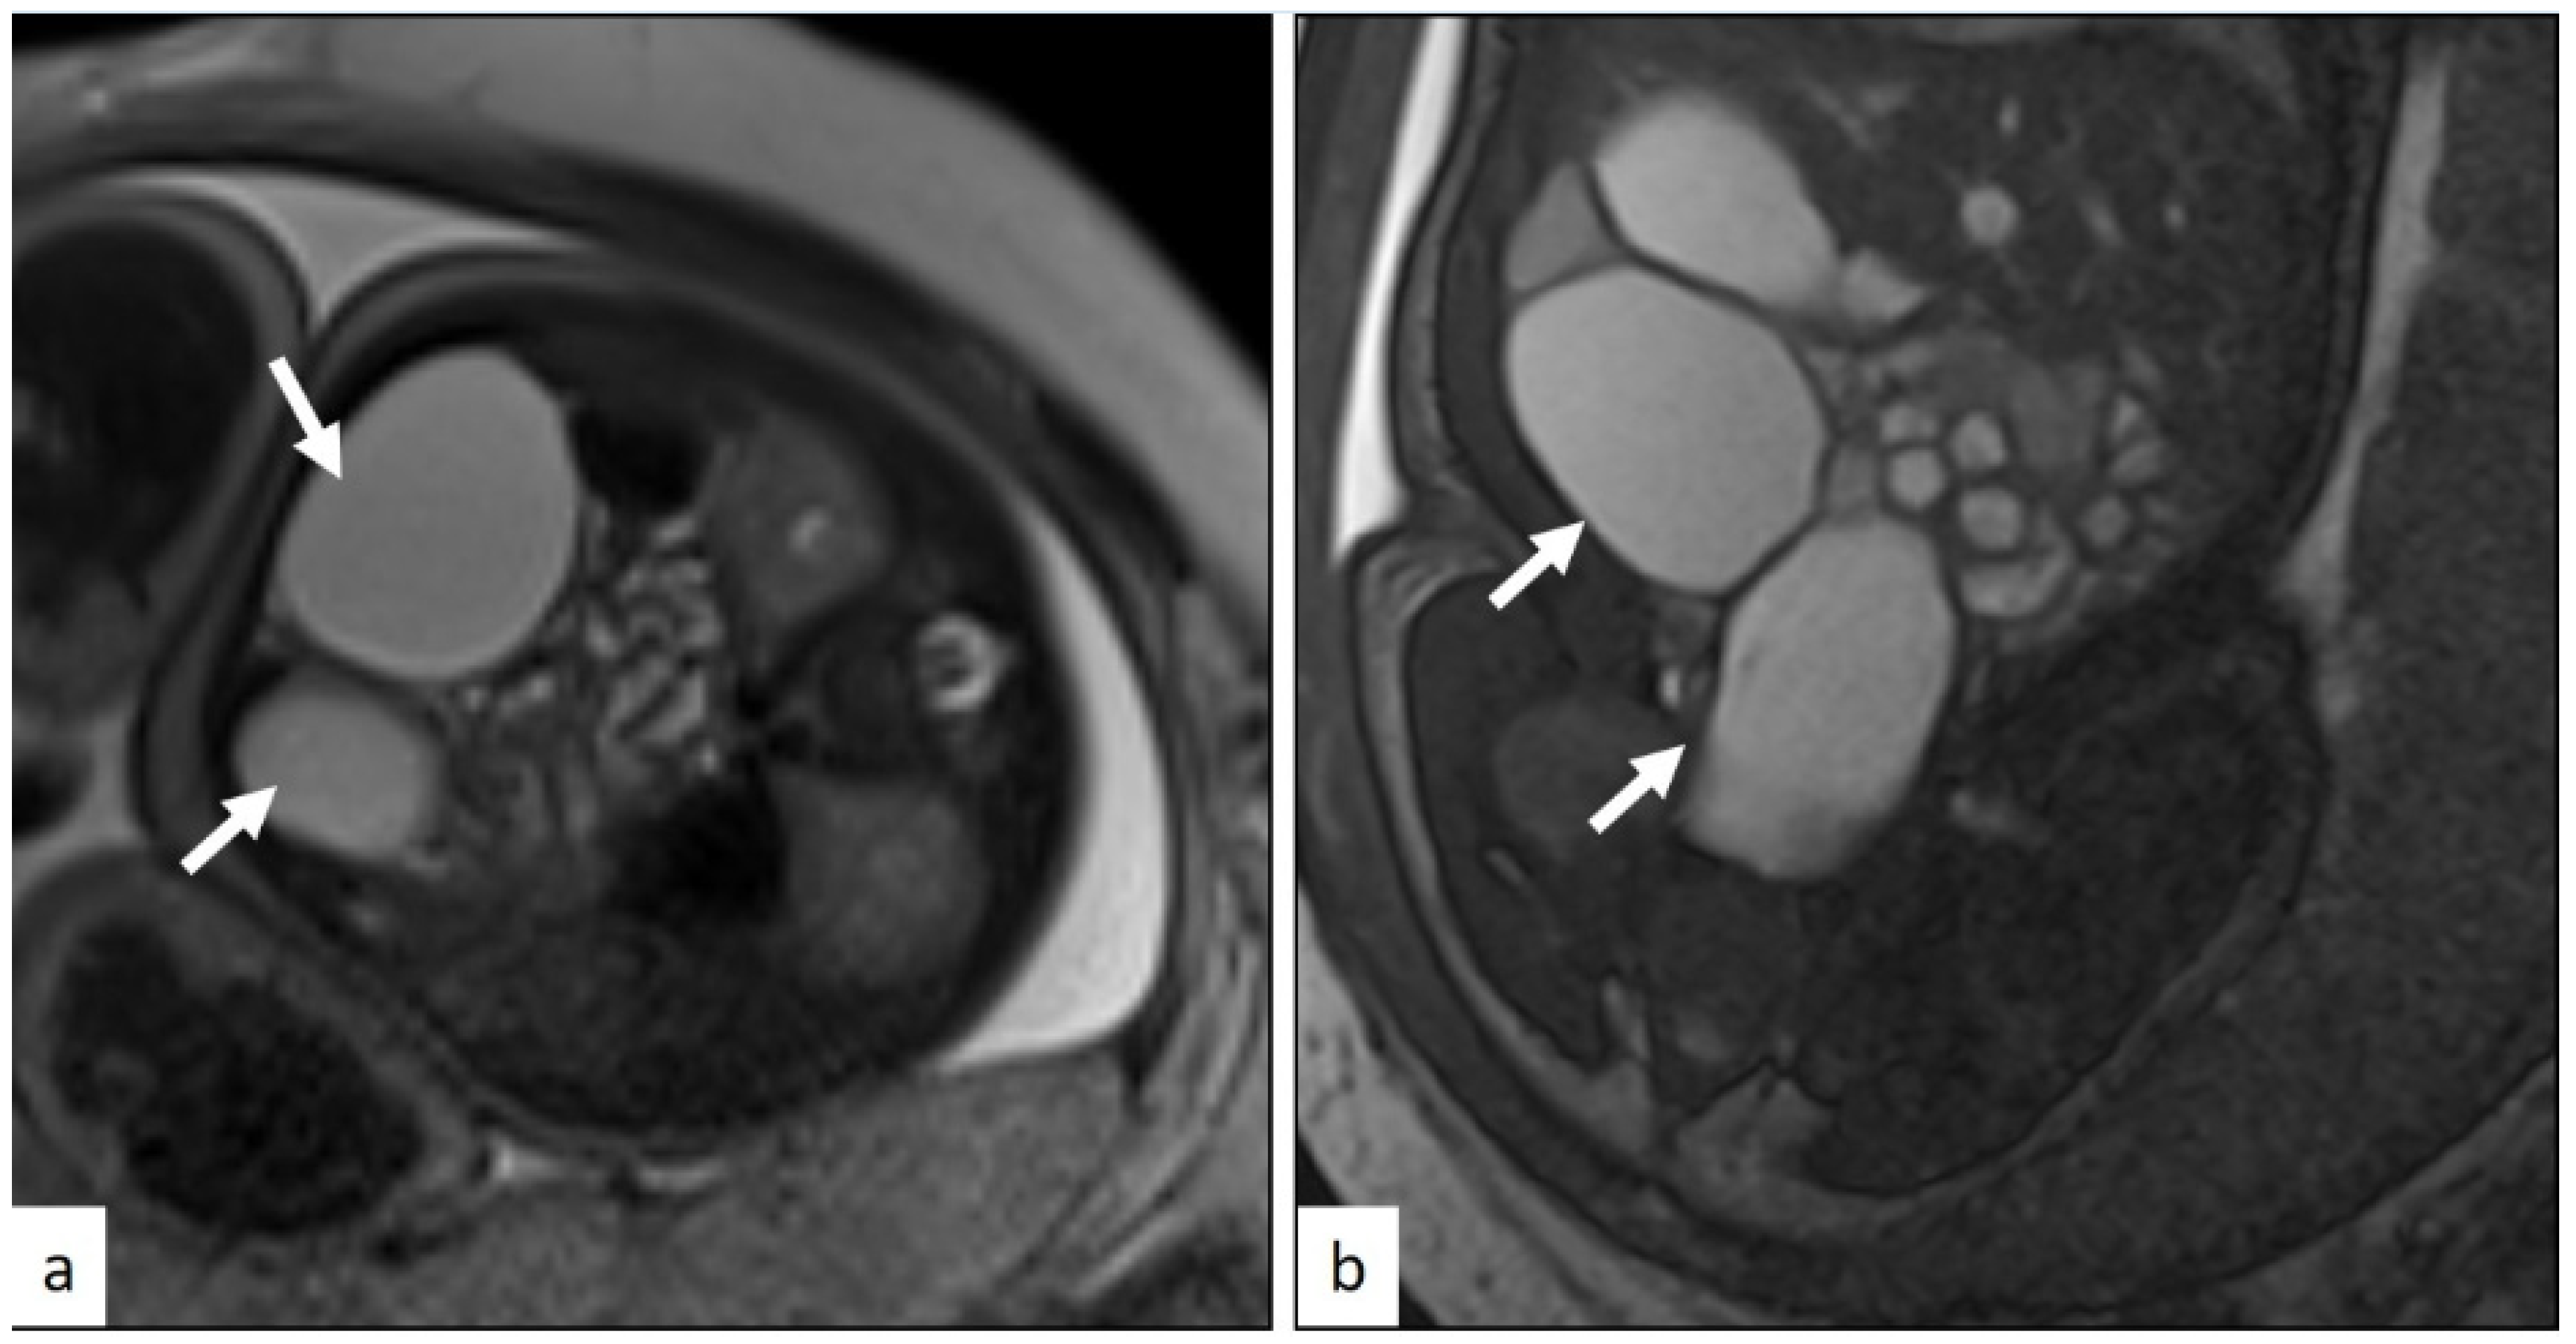

| Cardiac | 1 (20.0) | (3.6–62.4) | 0.194 | 0 (0.0) | (0.0–43.4) | 0.589 | 1 (20.0) | (3.6–62.4) | 0.563 |